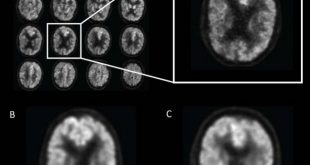

نوروسافاری | پژوهشگران انگلیسی، نوعی الگوریتم یادگیری ماشین ابداع کردهاند که میتواند آلزایمر را شش سال زودتر از پزشکان تشخیص دهد. پژوهشگران، نوعی الگوریتم یادگیری عمیق طراحی کردهاند که میتواند آغاز آلزایمر را تا شش سال زودتر از پزشکان تشخیص دهد. ابداع این الگوریتم، بخشی از پروژه فناوری یادگیری ماشین …